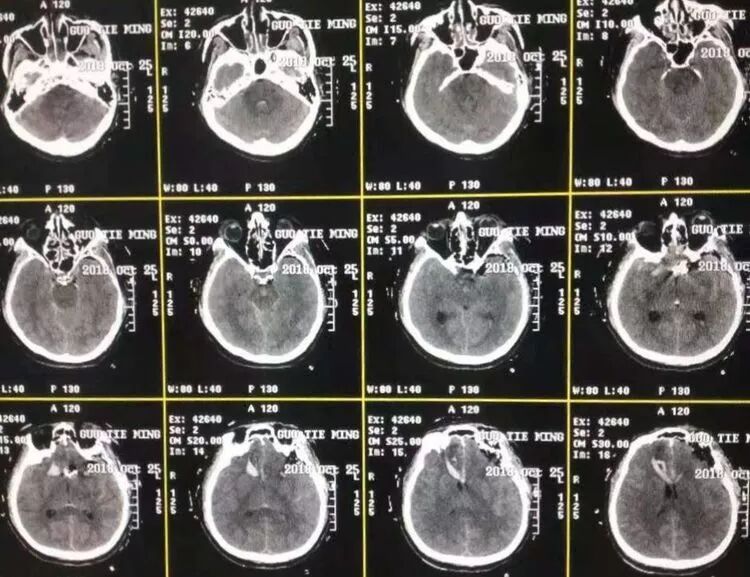

收治病人为SAH病例,CTA提示前交通动脉瘤,瘤顶指向后上方,瘤体较大。

考虑动脉瘤体积相对较大,瘤顶指向上方,瘤颈较宽,充分暴露是必要的。如果选择翼点和眶上外侧入路需要吸除部分同侧直回,可能有潜在的脑功能损伤风险,因此选择改良OZ入路完成手术。